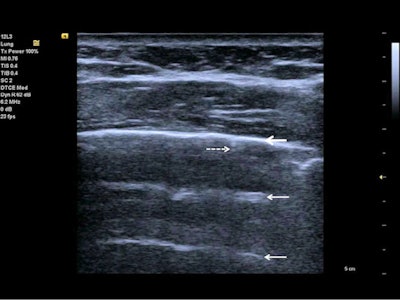

Follow-up of an intensive care unit patient with COVID-19 pneumonia after mechanical ventilation. An indirect sign of recovery is the appearance of A-lines (white arrows) through the recovery phase. No major pleural fragmentation (bold white arrow) is seen, but a mirror effect is visible (left white arrow). All figures courtesy of Dr. Dirk-André Clevert and colleagues and Insights into Imaging.

Follow-up of an intensive care unit patient with COVID-19 pneumonia after mechanical ventilation. An indirect sign of recovery is the appearance of A-lines (white arrows) through the recovery phase. No major pleural fragmentation (bold white arrow) is seen, but a mirror effect is visible (left white arrow). All figures courtesy of Dr. Dirk-André Clevert and colleagues and Insights into Imaging.Lung ultrasound in experienced hands can give results that are comparable to chest CT and even superior to standard chest radiography for assessment of pneumonia and/or adult respiratory distress syndrome (ARDS), they explained.

In the diagnosis of lung pathologies, ultrasound artefacts arising from the chest wall and pleural surface can provide valuable information and may correlate with the existing lung pathophysiology. There are two major ultrasound artefact patterns that a clinician may detect: "A-lines" and "B-lines," and in rare cases even "C-lines" are visible.

A-lines are reverberation artifacts triggered by oscillating tissue with an air interface, causing the ultrasound waves to be reflected strongly and to reverberate. Among the probe and lung surface, the ultrasound waves bounce back and forth. A-lines are parallel horizontal repetition lines of the pleural surface, appearing deeper on the display screen.